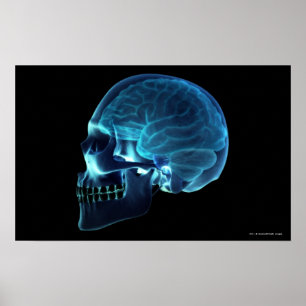

Röntgen från hjärnan inuti en skalle poster

Pris343,00 kr

Röntgen från hjärnan inuti en skalle canvastryck

Pris1 689,00 kr

Röntgen från hjärnan inuti en skalle vykort

Pris21,00 kr